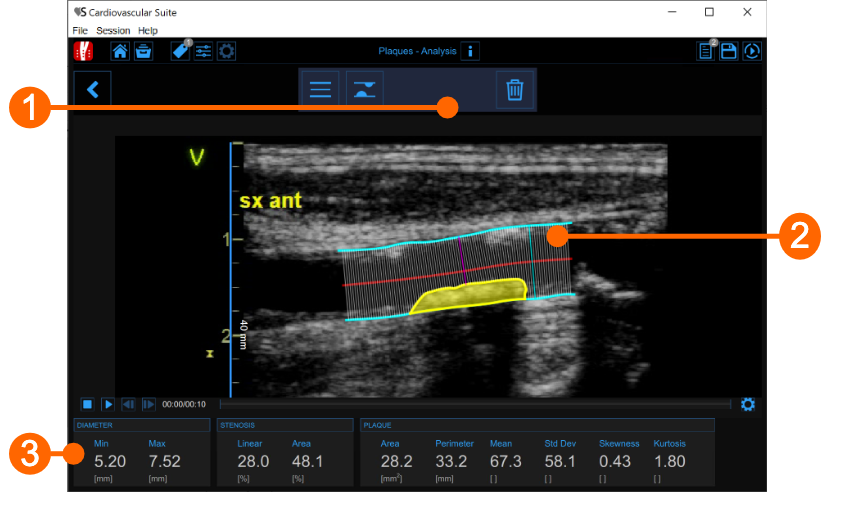

The plaque analysis window contains the following components:

1. Setup panel

It contains the controls for tracing of the vessel borders, drawing a plaque and delete it.

2. Plaque analysis tool

The Trace borders  button is used to manually trace the borders of the vessel. The user has to trace point-by-point the vessel edges and the software interpolates them. It is possible to modify the points by dragging them, as shown in the following picture.

After the two borders are traced, the software automatically compute the minimum and maximum values of the diameter and the linear and circular values of the stenosis. The Draw plaque  button is used to manually draw the profile of a plaque. The user has to trace point-by-point the plaque profile and the software interpolates them. Also in this case, it is possible to modify the points by dragging them and to delete a plaque, as shown in the following picture.

After the plaque is drawn, the software automatically computes its area, perimeter, and the mean, standard deviation, skewness, and kurtosis of its grey level.

3. Data panel

This panel contains the computed values. In particular, it shows the minimum and maximum values of the diameter and the linear and circular values of the stenosis. In addition, if a plaque has been drawn, it also displays its area and perimeter, and the mean, standard deviation, skewness, and kurtosis value of its grey level.